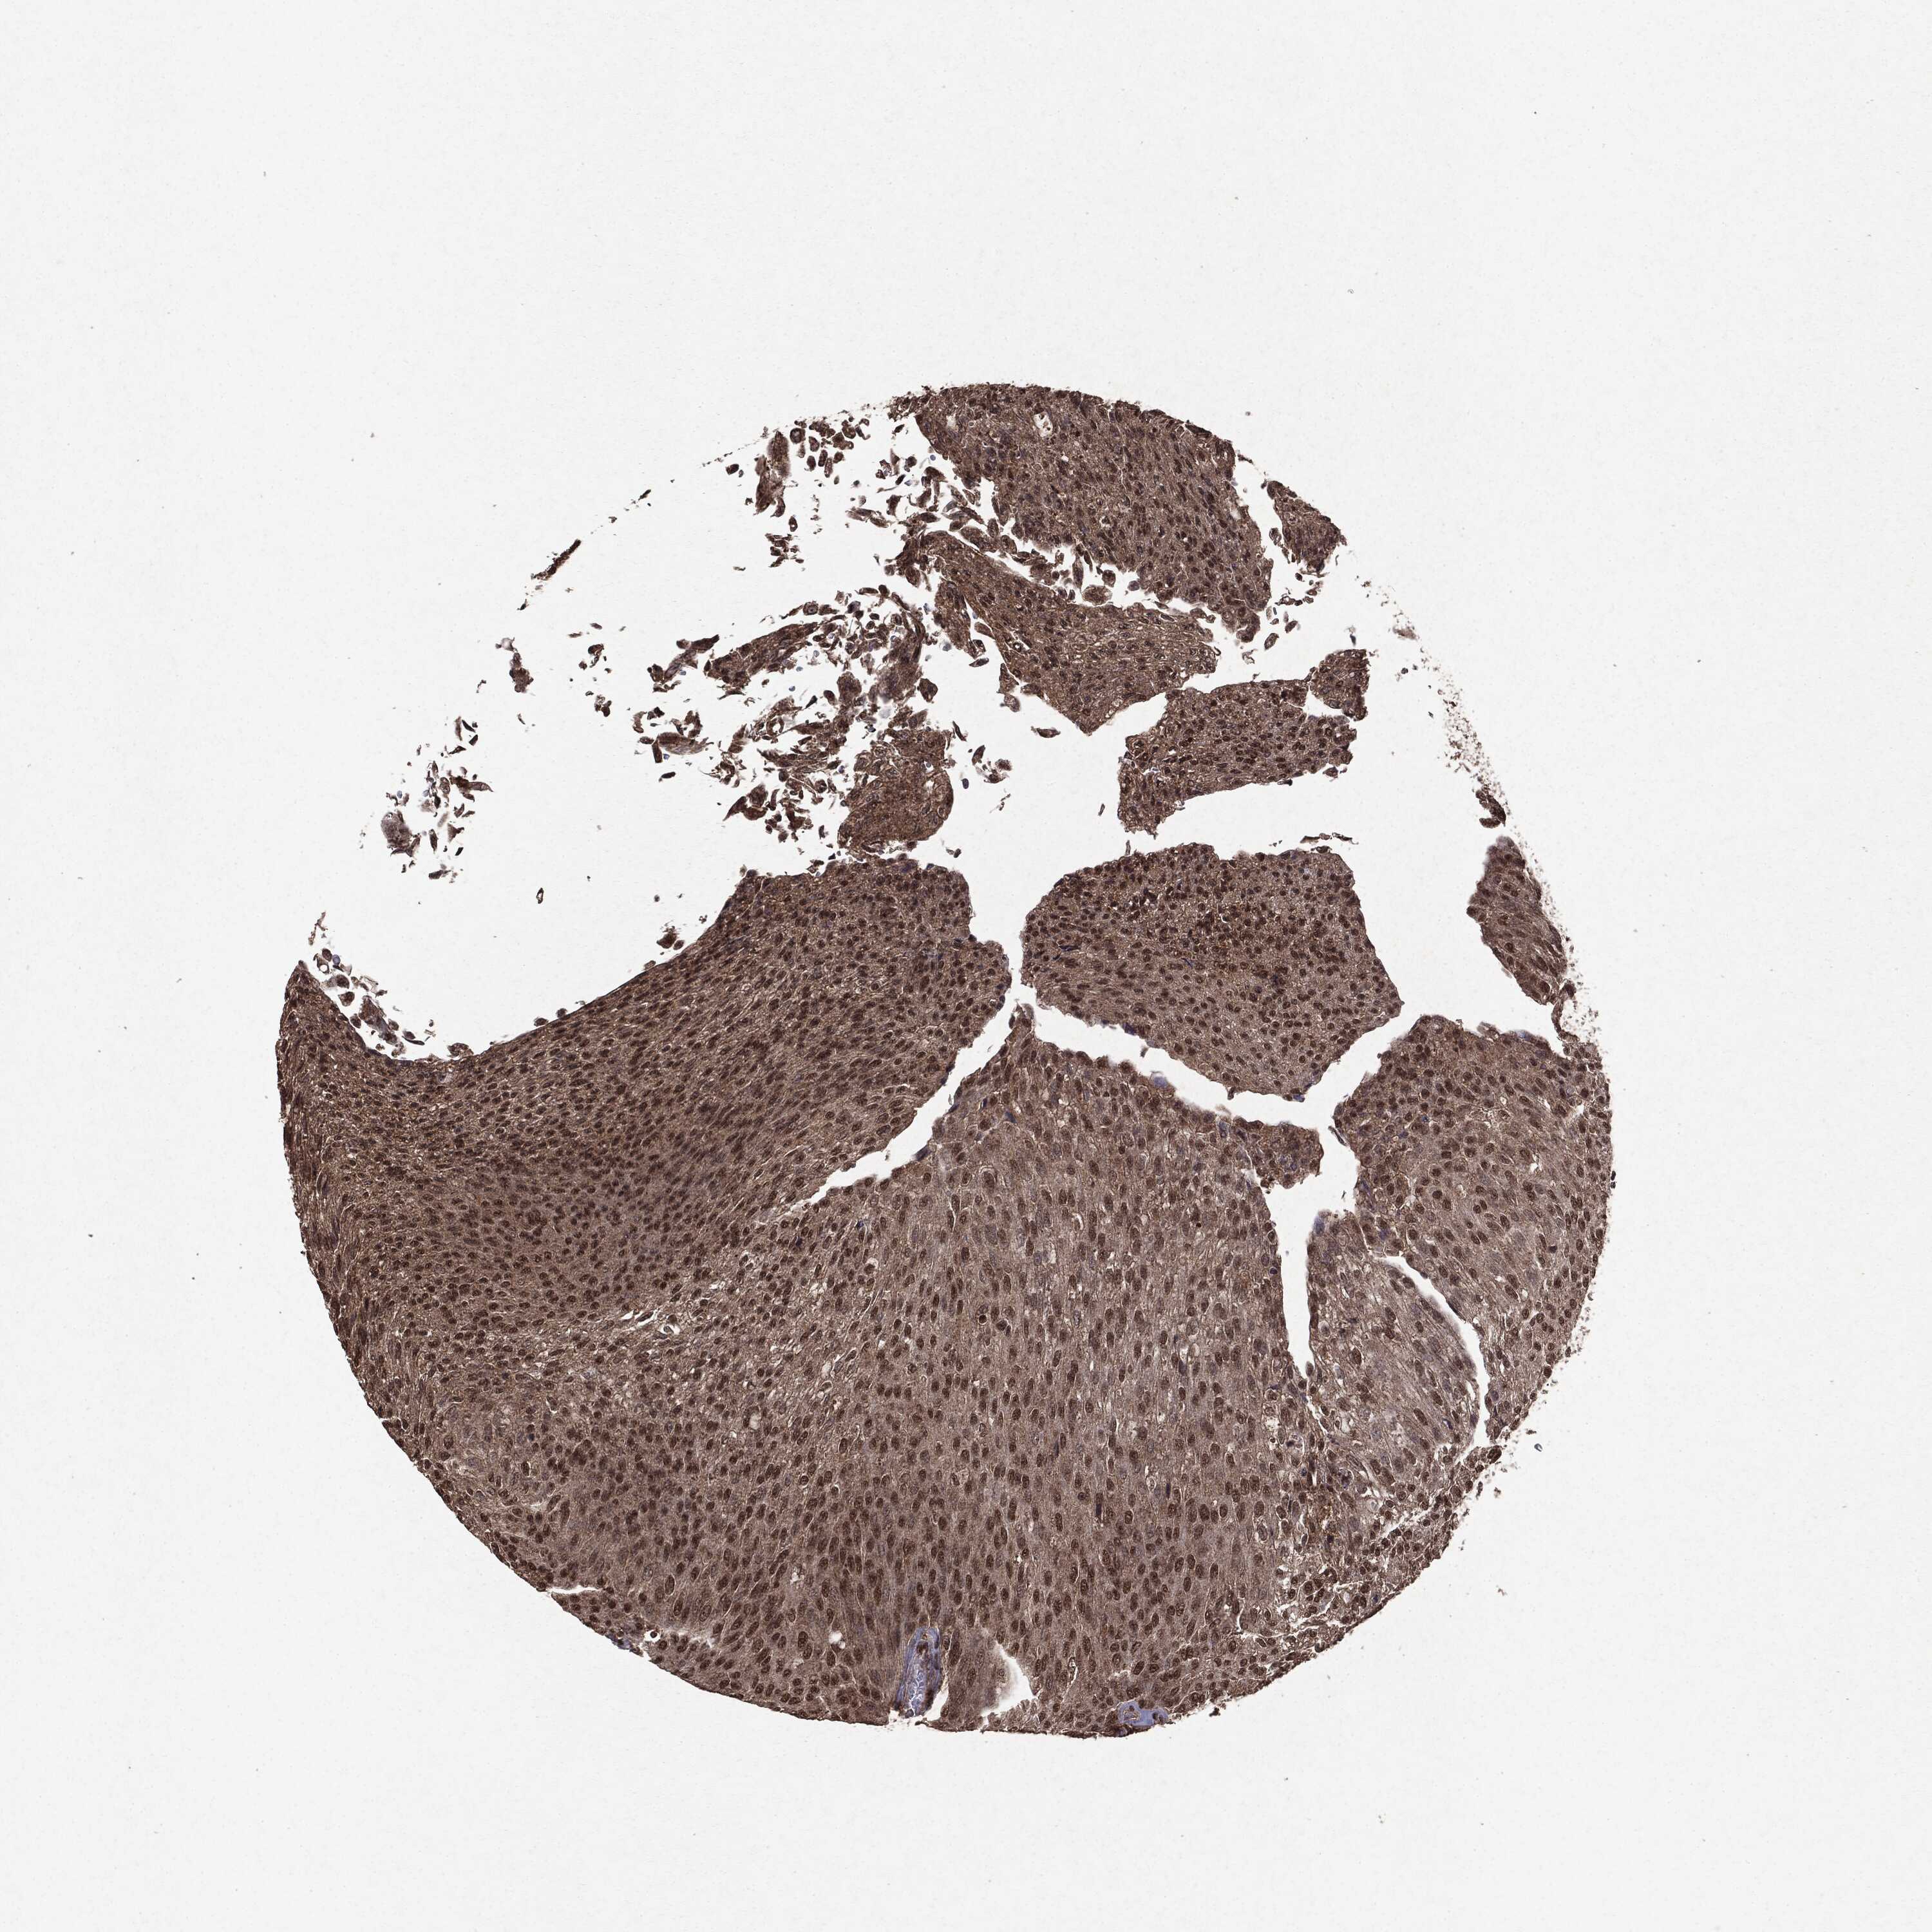

UROTHELIAL CANCER - Protein expressioni

A mouse-over function shows sample information and annotation data. Click on an image to view it in a full screen mode. Samples can be filtered based on level of antibody staining by selecting one or several of the following categories: high, medium, low and not detected. The assay and annotation is described here.

Note that samples used for immunohistochemistry by the Human Protein Atlas do not correspond to samples in the TCGA dataset.

Antibody stainingi

Antibody staining in the annotated cell types in the current human tissue is reported as not detected, low, medium, or high, based on conventional immunohistochemistry profiling in selected tissues. This score is based on the combination of the staining intensity and fraction of stained cells.

Each image is clickable and will lead to virtual microscopy that enables deeper exploration of all samples and also displays staining intensity scores, fraction scores and subcellular localization as well as patient and tissue information for each sample.

Antibody HPA008819

Urothelial carcinoma, High grade